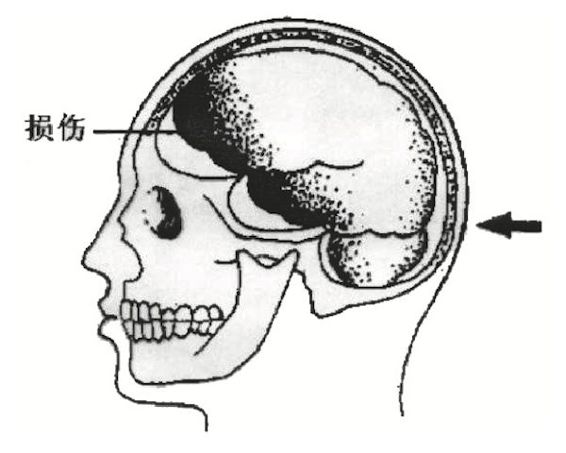

在一些高坠、摔跌事件中,死者的头颅一侧着地,和地面形成了碰撞,头皮会有血肿,颅骨可能会出现骨折,颅内会有相应的出血和脑挫伤。同时,在着地侧的对侧脑组织也会发生脑挫伤和出血。这就叫对冲伤。

法医学界认为,对冲伤是因为惯性作用形成的,是头颅减速运动(头颅从运动状态突然受力变成静止状态)中形成的特征性损伤。

有读者会问,一个人枕部和额部的脑组织都有脑挫伤和出血,那么会不会是他枕部被人打击,额部也被人打击所致呢?其实这个很好分辨。如果是打击或者碰撞,最先受到损害的是头皮,所以头皮会出现血肿。如果这个人枕部和额部的头皮都有血肿,那么这就不是对冲伤,而是两次加速运动——打击(头颅从静止状态突然受力而加速运动)所致。但是如果只有枕部有头皮血肿,额部仅有颅内出血,却没有头皮的血肿,说明额部的损伤不是打击直接造成的,而是摔跌枕部导致的对冲伤。